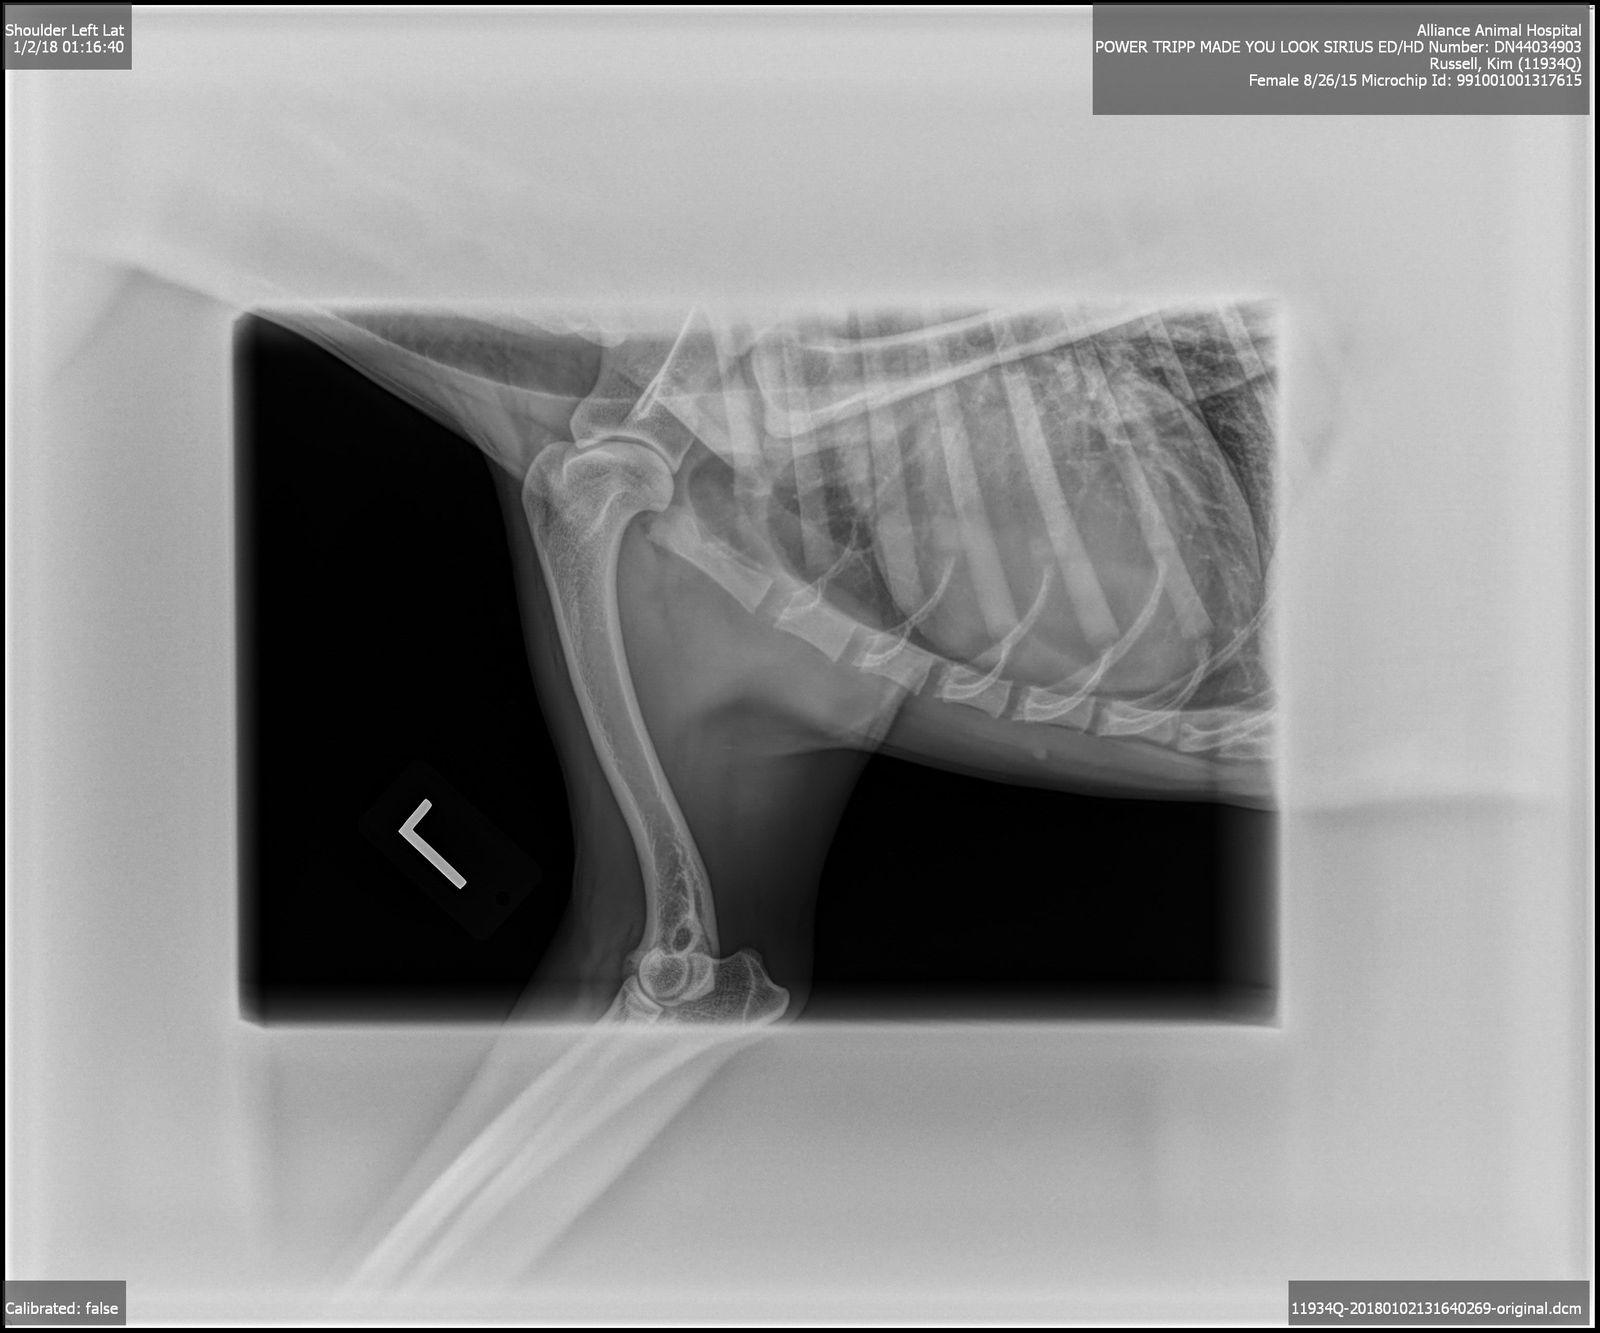

OFA Excellent, Shoulders and Elbows Normal, CEA/EAOD/CM/DM/MDR1/TNS/IGS/SN Normal,

2015/8/25AKC DN44034903 OFA Excellent, Shoulders and Elbows Normal, CEA/CM/DM/MDR1/TNS/IGS/SN Normal, BAER Normal